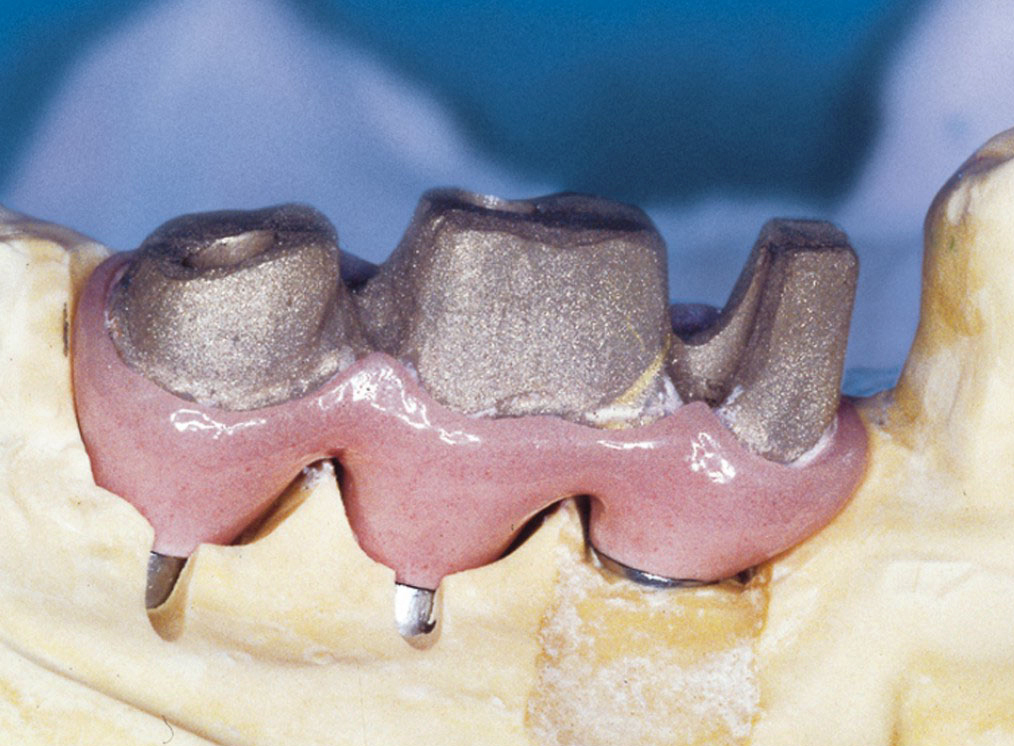

Protetické řešení může být pomocí můstku, který je kotvený na implantátech nebo pomocí jednotlivých korunek na implantátech.

V zásadě je možné do těchto můstků zařadit i přirozené zuby, zejména pokud je potřeba tyto zuby ošetřit proteticky – korunkami. Korunky nebo můstky mohou být na implantáty nacementovány nebo přišroubovány.

Pevné můstky – lepené nebo šroubované

Třmeny

Kulové attachmenty

Sub-Tec Locator®

S pomocí zubních implantátů můžeme díky různým kotevním systémům (třmeny, kulové hlavy, Locatory) zajistit stabilitu a držení protézy nebo při použití většího počtu implantátů zhotovit pevné náhrady – můstky nalepené nebo našroubované na pevno na implantáty.